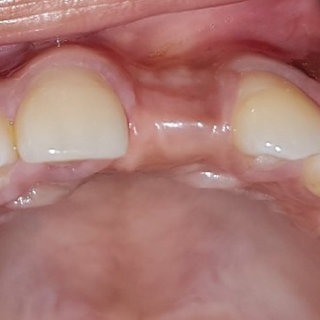

Pérdida de un diente único

La pérdida de un diente único es cuando un solo diente se ha caído o ha sido extraído, y se necesita un implante para reemplazarlo.

Los pacientes pueden notar un espacio donde solía estar el diente. Esta condición puede afectar la estética y la función masticatoria.

El tratamiento incluye la colocación de un implante dental para restaurar el diente perdido.